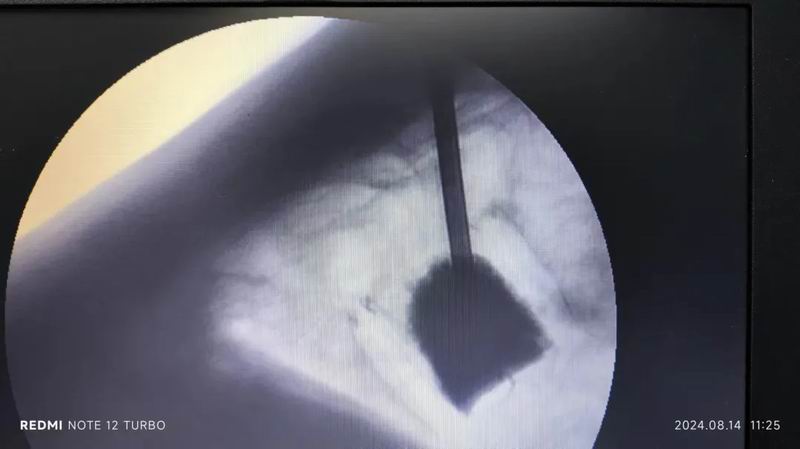

在精确的C臂引导下,骨科专家郭伯英与许主任携手并进,他们运用精湛的技术,通过特制的穿刺针精准地穿入患者椎体。随着默契的配合,骨水泥被准确无误地注入病变的椎体中。透视结果显示,骨水泥分布均匀,未见周边泄漏,标志着这次手术取得圆满成功。